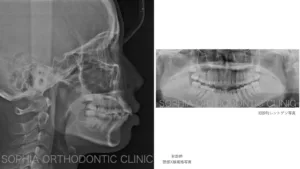

リンガル、前突.004